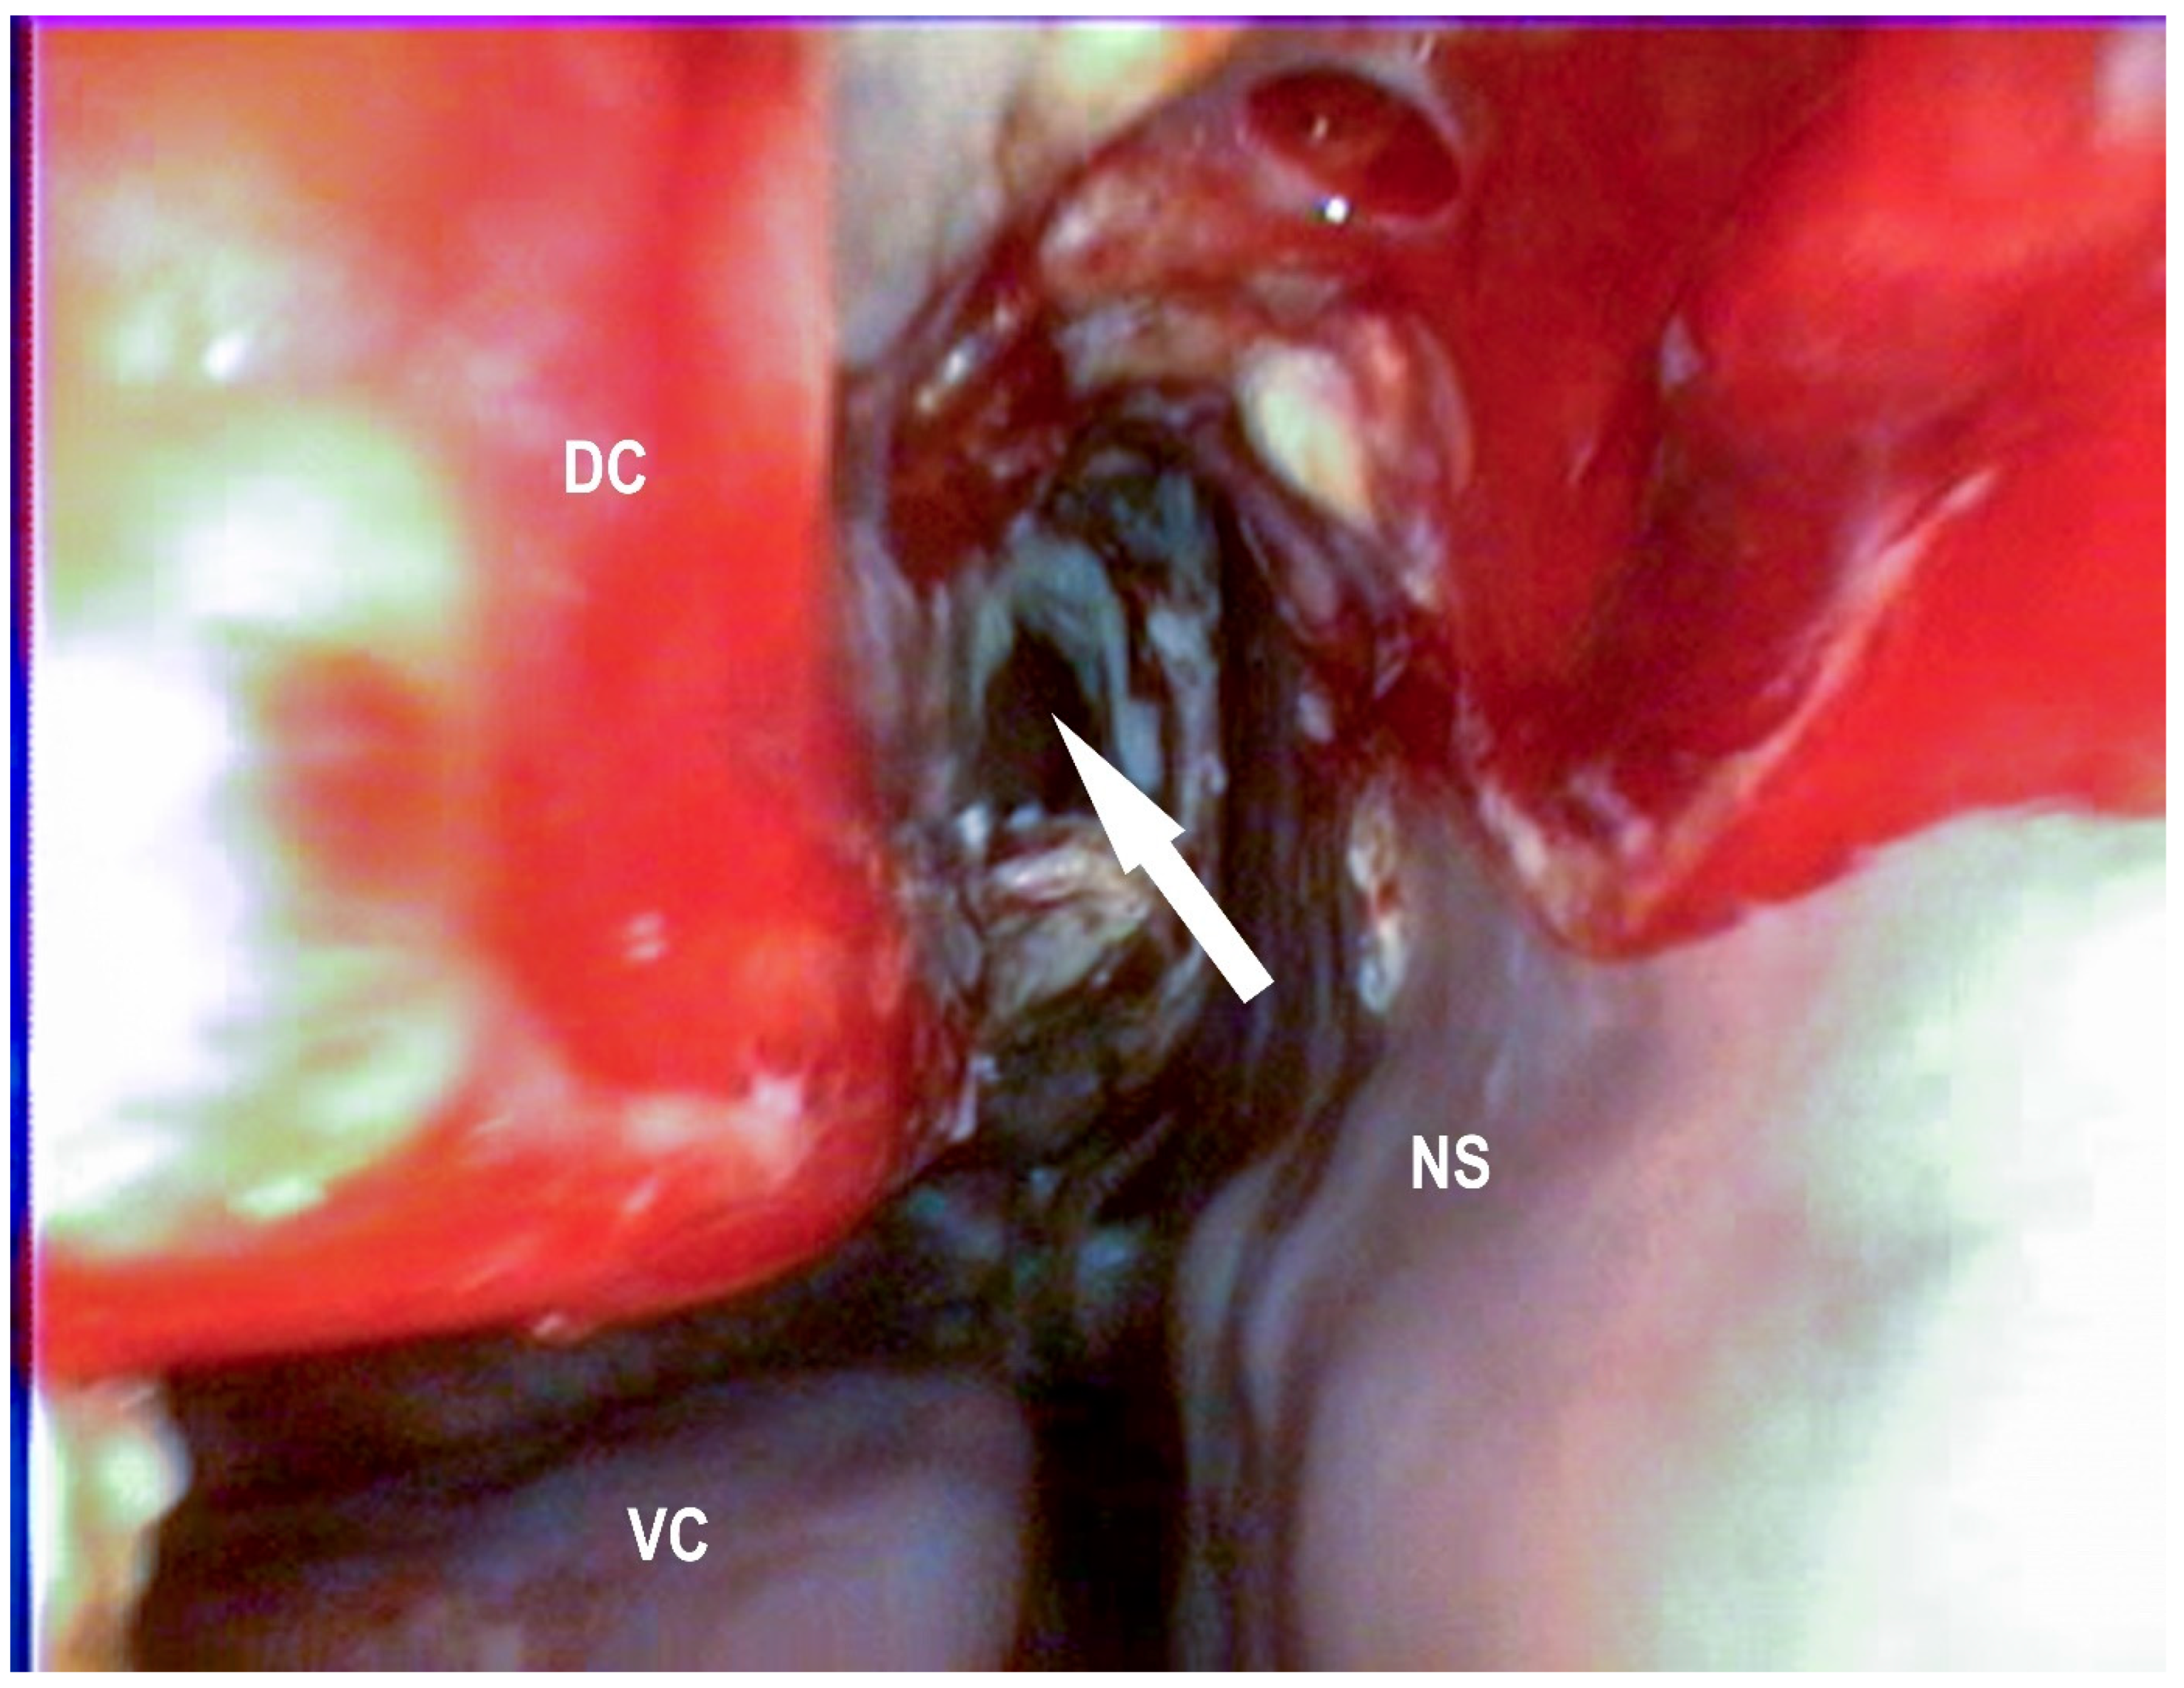

2.2.4. Endoscopic Guided Conchotomy

2.2.5. Transendoscopic Laser Fenestration of the Nasal Conchae

3.1.3. Conchotomy and Transendoscopic Laser Fenestration of the Bulla of the Maxillary Septum